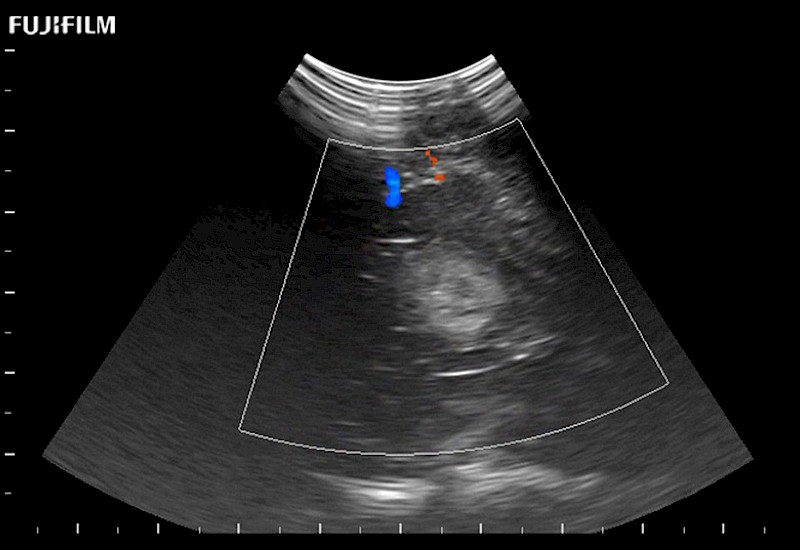

Hockey-stick linear array transducer is the transducer of choice for cervical spine scanning.

Main Specifications: